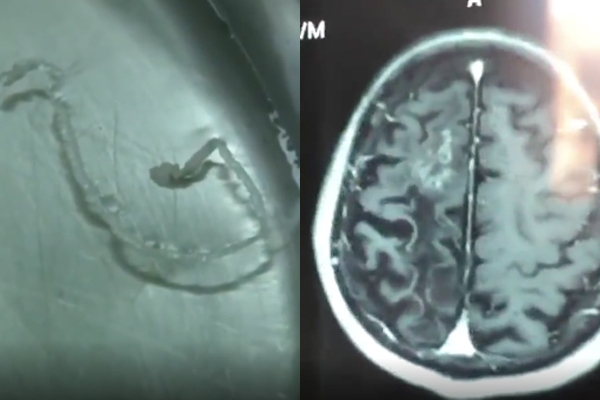

| Hình ảnh chụp MRI phát hiện tổn thương trong não (ảnh phải) và hình ảnh con sán ngoe nguẩy được gắp ra |

Hình ảnh chụp MRI cho thấy, thuỳ trán phải của ông có các nốt tổn thương. Xét nghiệm máu cho thấy có sự hiện diện của ký sinh trùng. Bác sĩ chỉ định phải phẫu thuật càng sớm càng tốt.

Sau phẫu thuật, các bác sĩ đã gắp ra con sán dài 10 cm, trong suốt và vẫn ngọ nguậy. Sau mổ, bệnh nhân hồi phục nhanh, các cơn đau đầu biến mất.